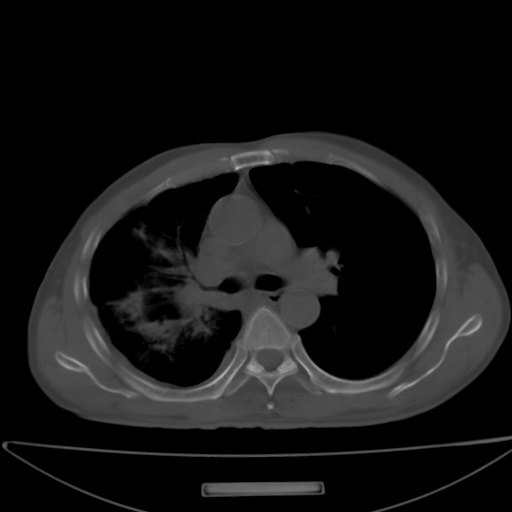

以下是引用jsgdoctor在2008-11-6 22:12:00的发言:[br]右主支气管壁明显增厚,管腔狭窄.考虑为右侧中央型肺癌伴阻塞性炎症\\肺脓肿.

以下是引用zjzjr在2008-11-6 20:25:00的发言:[br]中心型肺ca,合并阻塞性肺炎

以下是引用zsl6918在2008-11-6 19:43:00的发言:[br]右侧中心性肺癌(鳞癌)